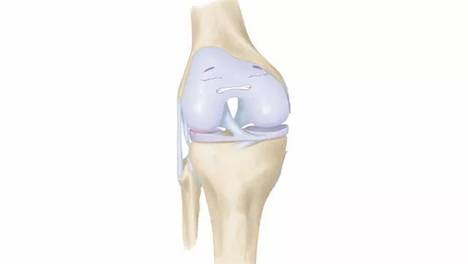

跑步膝小科普

如何避免给膝盖添麻烦?

20岁切除半月板,30岁就得了关节炎,半月板伤了到底该不该切?

膝盖有三层“保险”,如果一二层已失守,务必用好第三层!